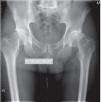

Se mide la distancia desde el centro de rotación a la parte superior del trocánter menor, en la cadera sana (fig. 4). Esta medida de longitud deberá respetarse de forma exacta en la cadera a operar para así, evitar dismetría9.